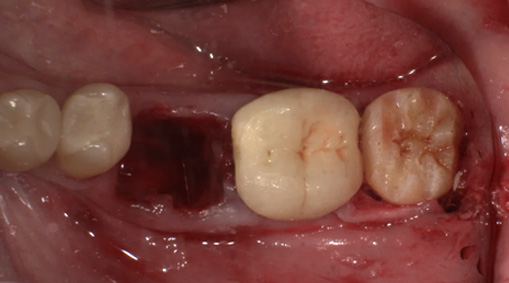

4-5日目 傷の消毒・経過観察を行います。

術後4週目の移植した歯牙。固定は維持されている。